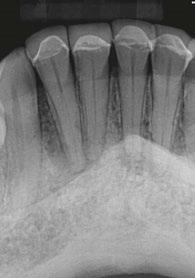

Treatment of severely atrophic maxillae often requires highly advanced procedures such as quad-zygomatic implants1-3 (Figure 1) or customized subperiosteal implants (Figure 2).4,5 Quad-zygomatic implant treatment has a long history of success, but requires significant surgical expertise due to limited malar bone availability and propinquity to anatomic structures such as the orbit and infraorbital nerve.6 Customized subperiosteal implants, on the other hand, are a promising new treatment option but have limited long-term follow-up data and significant expense.7 Transnasal dental implants have recently been introduced as another option for treatment of severely atrophic maxillae, specifically as an alternative to quad-zygomatic implant placement (Figure 3).8 Transnasal implants may serve as a replacement for anterosuperior zygomatic implants as they tangentially traverse the interior lateral nasal wall and achieve high insertion torque via 3 mm-5 mm of apical engagement in the confluence of the inferior concha, lateral nasal wall, and frontal process of the maxilla (Figure 4).8-16

In 2019, the first report on transnasal implants, called the Vanderlim technique, was published in Brazil as an alternative to the quad-zygomatic implant configuration.8 In this publication, the authors described using 16 mm–25 mm long implants placed tangentially along the interior of the lateral nasal wall to achieve insertion torque of 40-50 Ncm for immediate loading. In 2021, Almeida published a case report documenting use of an “extralong transnasal implant” as an alternative to the quad-zygoma,10 and Vanderlim supported his 2019 publication with a series of 12 cases using “transnasal implants placed using the Vanderlim technique” with follow-up of 2-26 months.9 In 2023, Holtzclaw published a textbook with a case series of seven transnasal implant cases performed by himself and other dental implant surgeons.6